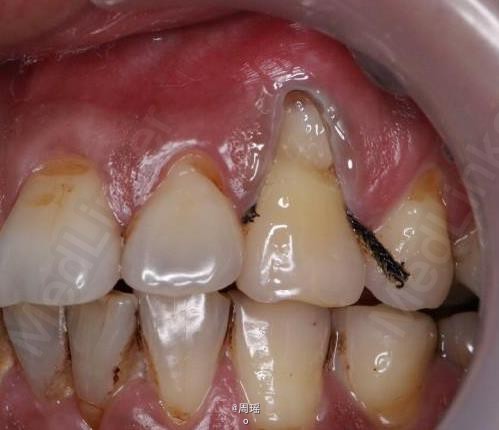

楔状缺损的充填

楔状缺损

患者,男,40岁,左上第一前磨牙楔状缺损来诊。平素体质一般,无系统性疾病和高血压、心脏病等病史,无药物、食物过敏史。